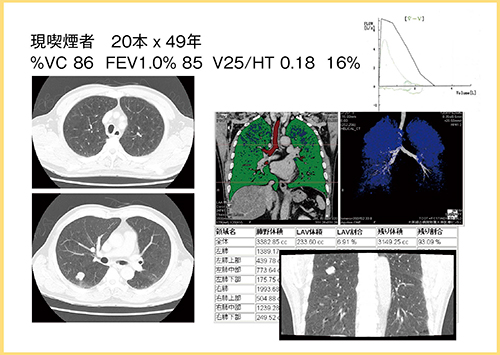

症例1は現喫煙者の患者で,肺実質内に気腫が目立ち,Flow Volume Curveからはかなり気流の制限があることがわかる(図3)。動態撮影をよく見ると,左右の横隔膜の動きにズレがあることからも気流の制限が疑われる。4D気管支トラッキングで解析すると,左下葉の気管支断面が,呼気時に非常に強く狭窄することが観察された(図4)。

呼吸状態の良い気腫症例と比較すると,気管支の動態がかなり異なることから,気管支動態はFlow Volume Curveや症状と相関する可能性があると考えられる。

図3 症例1の動態撮影画像

(120kV,8mAs,AIDR 3D)